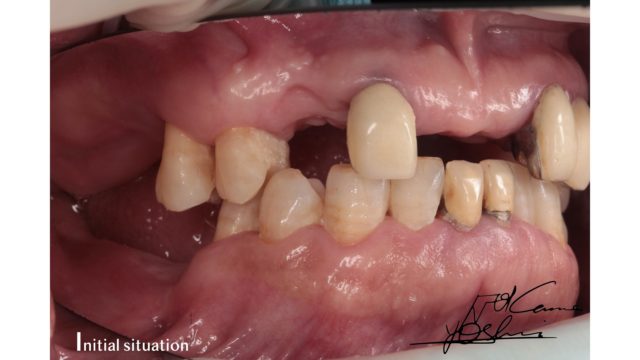

お口の左側、BEFORE写真です。

お口の左側、AFTER写真です。